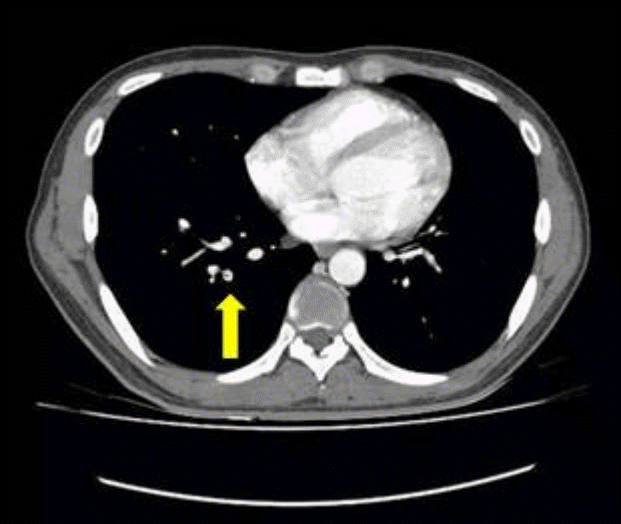

Figure 2.

Computed tomography of the chest revealed pulmonary thromboembolism of the right pulmonary artery (arrow).